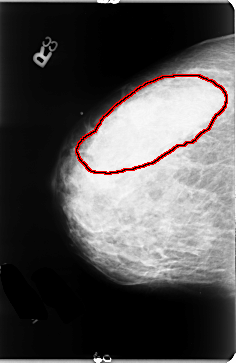

FILE: B_3061_1.RIGHT_MLO.OVERLAY

TOTAL_ABNORMALITIES 1

ABNORMALITY 1

LESION_TYPE CALCIFICATION TYPE PLEOMORPHIC DISTRIBUTION REGIONAL

LESION_TYPE MASS SHAPE FOCAL_ASYMMETRIC_DENSITY MARGINS N/A

ASSESSMENT 5

SUBTLETY 3

PATHOLOGY MALIGNANT

TOTAL_OUTLINES 1

BOUNDARY